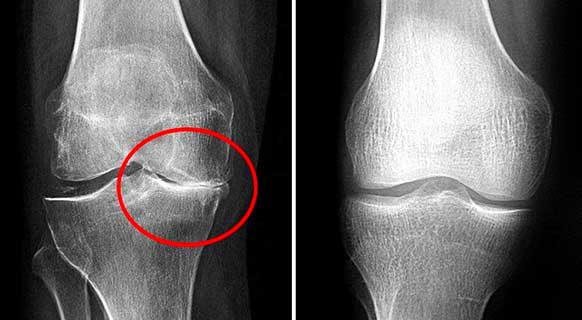

รูปภาพ: ภาพรังสีเอกซ์ของข้อเข่าก่อนและหลังทานแคปซูล Movinix

Movinix เป็นผลิตภัณฑ์ที่ดีมากสำหรับโรคข้อเสื่อม! ได้ส่วนลดมา ทั้งๆ ที่หมอของฉันไม่แนะนำ ตอนนี้หมอถึงกับแปลกใจเลยค่ะ! เขาเห็นความคืบหน้าจากภาพเอ็กซ์เรย์ด้วยค่ะ! ฉันจะทานให้ครบตามคอร์ส แล้วดูว่าเขาจะพูดอะไรอีก